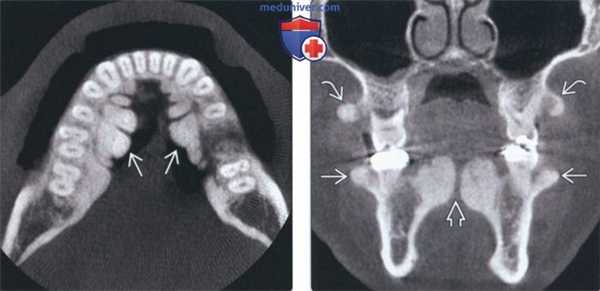

(Справа) На аксиальной 3D КЛКТ визуализируются множественные экзостозы с щечной стороны верхней челюсти в области моляров и премоляров. Столь многочисленные экзостозы можно удалить, т.к. они способны привести к функциональным нарушениям. Видна также щечная «губа» в передних отделах верхней челюсти.

4. КТ при щечных и небных экзостозах челюсти:

• КЛКТ:

о Экзофитные участки внешне не измененной костной ткани возле альвеолярного гребня

(Слева) На корональной КЛКТ определяются щечный и небный экзостозы в задних отделах верхней челюсти. Небный экзостоз иногда называют верхнечелюстным валиком. Обратите внимание на маленький небный валик, который часто появляется вместе с экзостозами.

(Справа) На аксиальной КЛКТ определяются множественные щечные экзостозы в области премоляров нижней челюсти Присутствуют также выбухающие нижнечелюстные валики. Частота экзостозов наивысшая при наличии нижнечелюстного и небных валиков одновременно.

(Справа) На корональной КЛКТ визуализируется маленький небный валик в средних отделах неба. Обратите внимание на небный экзостоз. Экзостозы часто сочетаются с небными валиками.

3. КТ при небном валике:

о Экзофитные срединные гиперденсные разрастания твердого неба

(Слева) На корональной КЛКТ визуализируется большой небный валик, разделенный посередине. Такие крупные валики могут приводить к нарушению функции и часто приводят к хронической травматизации, требуя удаления хирургическим путем. Покрывающая слизистая оболочка обычно истончена.

(Справа) На аксиальной КЛКТ у этого же пациента визуализируется мультицентрический небный валик. Обратите внимание на признаки доброкачественного роста: симметричное увеличение и ровные края.

4. КТ при нижнечелюстном валике:

о Двухсторонние экзофитные участки высокой плотности с язычной стороны в области премоляров нижней челюсти

(Слева) На аксиальной КЛКТ визуализируются большие фестончатые рентгеноконтрастные разрастания, представляющие собой нижнечелюстные валики.

(Справа) На корональной КЛКТ определяется сдавление языка огромными нижнечелюстными валиками. Валики покрыты тонкой слизистой оболочкой, которая может травмироваться. При хроническом воспалении или нарушении функции валики удаляются. Обратите внимание на верхне и нижнечелюстные щечные экзостозы, которые часто сочетаются с нижнечелюстными валиками.